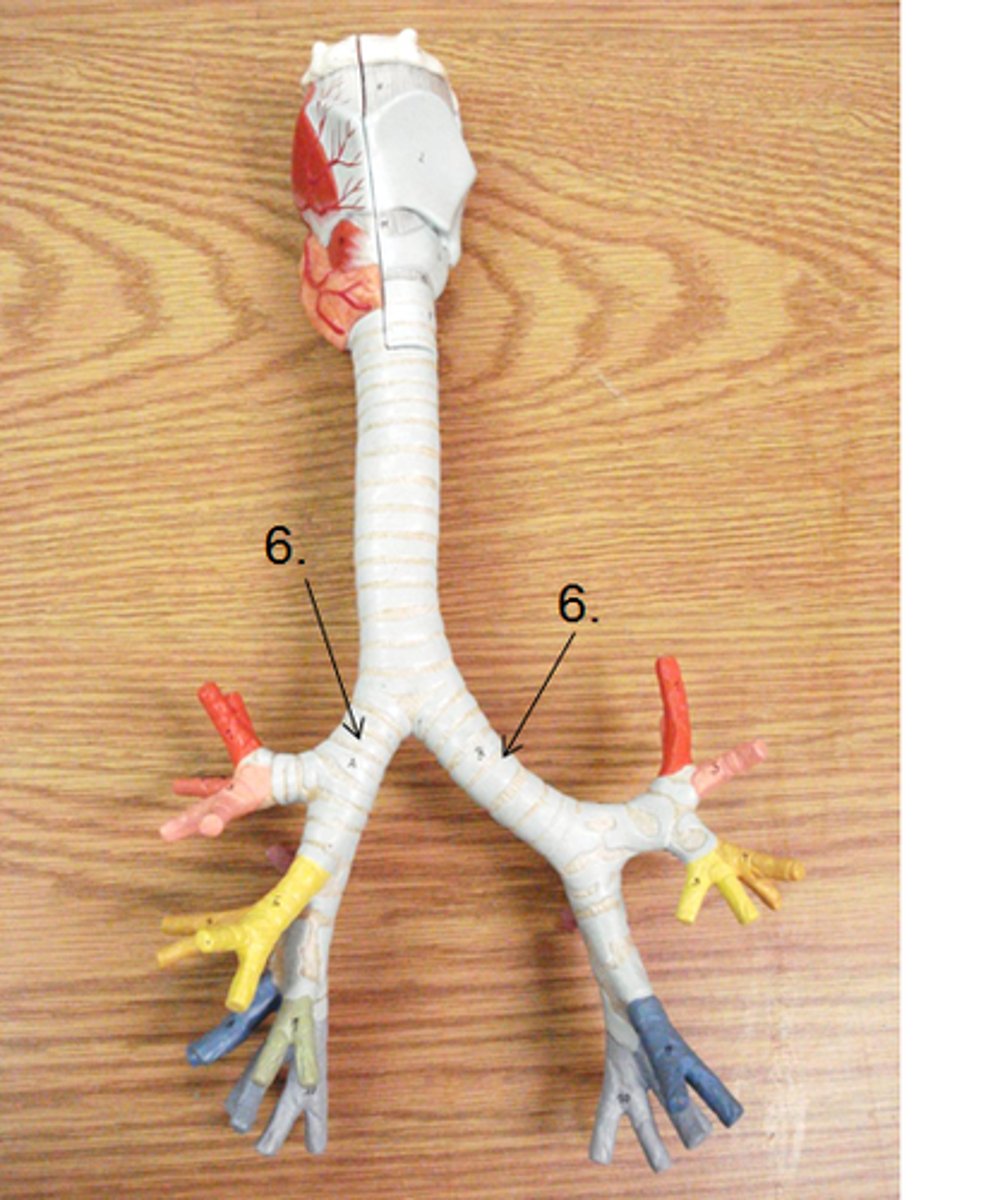

primary bronchus

The first branches of the trachea. There are two primary bronchi, one for each lung.

secondary (lobar) bronchus

The primary bronchi split into these smaller tubes within the lungs

tertiary (segmental) bronchus

branches of the secondary bronchi that divide into bronchioles; also called segmental bronchi

bronchial tree

collective name for the multiple branches of the bronchi and bronchioles of the respiratory system